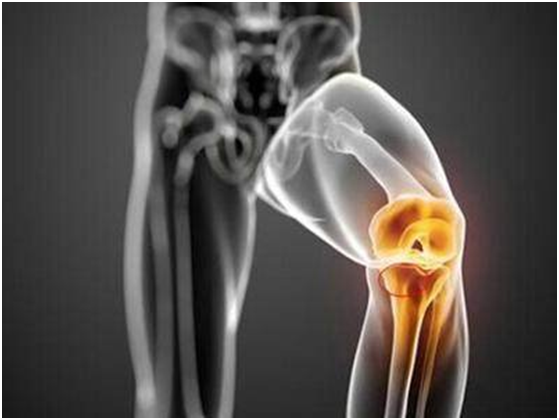

骨瘤指的是骨关节肿瘤,是指在骨关节里生长的肿瘤或新生物,包括原发性和继发性肿瘤以及一些瘤样病变。祖国医学对骨关节肿瘤的记载最早可追溯到殷商时代,殷墟甲骨文就有“瘤”的病名。《灵枢•刺节真邪》曰:“有所结,气归之,津液留之,邪气中之,凝结日以易甚,连以聚居,为昔瘤,以手按之坚。 明•薛已《外科枢要•卷三》曰:“若伤肾气,不能荣骨而为肿者,其自骨肿起,按之坚硬,名曰骨瘤”。认为肾虚可致骨肿瘤形成,主张用地黄丸同补中益气汤进行治疗。清•吴谦《医宗金鉴•外科心法要诀•瘿瘤》曰:“瘤者,随气留住,故有是名也。多外因六邪,荣卫气血凝郁,内因七情,忧恚怒气,湿痰瘀滞,山岚水气而成,皆不痛痒。形色紫黑,坚硬如石,疙瘩叠起,推之不移,昂昂坚贴于骨者,名骨瘤。骨瘤尤宜补肾散坚,行瘀利窍,调元肾气丸主之”。 从以上历代医家的论述可以看出,虽然祖国医学对骨关节的肿瘤没有现代医学的详尽分类、治疗,但已经明确把骨肿瘤和其他肿瘤、骨病区分开来。认识到良性肿瘤与恶性肿瘤的不同以及这些肿瘤基本的病因病机、临床诊断、治疗方法和预后。1.病毒学说,肉瘤病毒制成大白鼠的骨肉瘤;用肉瘤的无细胞提炼物可以在正常人体细胞内诱导出肉瘤的特异性抗体。这些研究发现使许多学者认为病毒与人体肉瘤的发生相关。2.慢性刺激学说,在物理因素中,凡发生辐射,如X线、镭、放射性核素等,经体内或体外放射,均可导致肿瘤;动物实验证明某些化学物质(甲基胆蒽)可诱发骨肉瘤;碳氢类、芳香染料和偶氮染料等可产生纤维肉瘤。3.胚胎组织异位及残存学说,人们观察发现,胚胎异位或残存,经某种刺激后向肿瘤转化。4.遗传(基因)学说,正常细胞基因发生改变产生肿瘤细胞,瘤细胞继续增殖,且将其生物特性遗传。5.恶变学说,良性骨肿瘤及瘤样病变,如良性成骨细胞瘤、软骨瘤、骨软骨瘤等良性肿瘤可恶变为肉瘤。1、加强锻炼:体育锻炼可以起到强身健体的作用,提高机体免疫力,抵御一些病毒感染,特别是一些DNA肿瘤病毒或者是RNA肿瘤病毒。2、避免外伤 :外伤可能会诱导骨肿瘤,应尽量避免,特别是在运动时,一定要做好防护,如果不慎受伤,要及时妥善处理。3、饮食预防与调理改变不良生活习惯:少吃或不吃亚硝酸盐浓度高的酸菜、咸鱼等,少吃苯并芘含量高的烘烤熏制及油炸食品,少食带有较多黄霉曲素、发霉、发酵的食物。4、避免放射辐射:经常接触放射性辐射,容易诱发骨肿瘤,尤其是青少年,正处于骨骼发育时期,经常接触,不利于骨骼健康。5、保持健康心态:遇事不急、不躁、不怒,善于调节情绪,心态积极向上。6、定期进行体检:复查肝肾功、血常规、肿瘤系列,如有异常应及时进一步检查。

(1)要早期发现骨肿瘤,可以通过抽血以及相关辅助检查来明确诊断。抽血主要是进行一些肿瘤标志物的抽血检查。(2)如果是较大的肿物,常规进行X线便可观察到肿物的存在。但如果是一些较小的肿物,还需要通过CT或磁共振来明确诊断,必要时甚至还可以进行PET-CT检查来明确全身是否有多发肿瘤。(3)在发现肿瘤后,可以在X线、CT、B超介导下取肿瘤组织进行活检,明确其良恶性,但有时如果肿物较小,很可能会取到正常的组织,所以必要时需要进行手术切除肿物来进行病理检查。(1)疼痛,为骨肿瘤早期出现的主要症状,病初较轻,呈间歇性,随病情的进展,疼痛可逐渐加重,发展为持续性。多数患者在夜间疼痛加剧以致影响睡眠。其疼痛可向远处放射。(2)肿胀或肿块,位于骨膜下或表浅的肿瘤出现较早,可触及骨膨胀变形。如肿瘤穿破到骨外,可产生固定的软组织肿块,表面光滑或者凹凸不平。(3)功能障碍,骨肿瘤后期,因疼痛、肿胀而患部功能将受到障碍,可伴有相应部位肌肉萎缩。(4)压迫症状,向颅腔和鼻腔内生长的肿瘤,可压迫脑和鼻的组织,因而出现颅脑受压和呼吸不畅的症状;盆腔肿瘤可压迫直肠与膀胱,产生排便及排尿困难;脊椎肿瘤可压迫脊髓而产生瘫痪。(5)畸形,因肿瘤影响肢体骨骼的发育及坚固性而合并畸形,以下肢为明显。(6)病理性骨折,肿瘤部位只要有轻微外力就易引起骨折,骨折部位肿胀疼痛剧烈,脊椎病理性骨折常合并截瘫。(7)全身症状,骨肿瘤后期由于肿瘤的消耗、毒素的刺激和痛苦的折磨,可出现一系列全身症状,如失眠、烦躁、食欲不振、精神萎靡、面色苍白,进行性消瘦、贫血、恶病质等。(1)局部肿块:为最早出现的症状,表现为坚实而无压痛,表面光滑,可为单发,也可为多发医`学教育网搜集整理。(2)疼痛:大多数良性骨肿瘤没有疼痛,少数除外(如骨样骨瘤)。(3)生长缓慢:肿瘤增大较慢,可在很长时间内肿瘤无变化,若肿物生长突然加快,要考虑恶变可能。(4)病理性骨折:少见,多发生于髓内病变者(如骨囊肿、骨纤维结构不良等)。(5)X线表现:肿瘤边界清楚、整齐,与正常骨有清晰的界限,常见有一反应性致密带;肿瘤一般不浸润软组织;有些肿瘤局部可呈囊性膨胀性骨质破坏;骨膜反应增生少见。(1)疼痛:关节附近出现固定性、持续性及渐进性的疼痛为恶性骨肿瘤最早出现的症状,夜间痛比较明显,疼痛突然剧烈可能是由于病理性骨折所致。(2)肿块:增大迅速,常伴有局部皮肤发热,浅静脉怒张,肿块边界不清(5)局部压迫症状:明显,常因肿瘤生长迅速压迫周围神经、血管而出现相应压迫症状。(6)实验室检查:血清碱性磷酸酶升高多见于恶性骨肿瘤如骨肉瘤。(7)X线表现:肿瘤破坏区边界毛糙不清;破坏区轮廓完整,骨皮质残缺不全;肿瘤可突破骨皮质及骨膜在软组织内形成肿块;破坏区可见形态数量不一、分布紊乱及轮廓模糊的瘤骨或钙化征象;常见骨膜反应增生。(1)骨软骨瘤:这些肿瘤占所有良性骨肿瘤的40%以上。它们主要存在于儿童和青少年中。骨软骨瘤是一种生长异常,发现于长骨的生长末端。骨软骨瘤可能单独生长,也可能伴有其他类似的肿瘤。(2)破骨细胞瘤:也被称为骨巨细胞瘤。长管状骨约占75-90%、长骨的骨端约占98-99%、膝关节周围约占55%。20-50岁:占80 % 15-20岁:占10%,<15岁:占2%,骨骺闭合后:98%,骨骺闭合前:占2%。(3)骨样骨瘤:多发生于5~20岁的儿童和青少年,男女发病率之比约为2:1。最常见的发病部位在下肢长骨,其次是上肢骨,脊柱、手、足等部位则较少见。(4)内生软骨瘤:它是始于软骨的骨肿瘤。它主要存在于骨骼内层的软骨中。脚和手的短骨受影响最大。青少年比其他年龄组受影响更大,大多20岁以后发病(5)非骨化性纤维瘤:常见于儿童及青少年,属于常见的发育异常,约35%的儿童会发生,5~20岁最多见。40%位于股骨远端,40%位于胫骨近端,10%位于腓骨。(1)骨肉瘤:最常见的原发恶性骨肿瘤,多发于10-20岁阶段青少年,好发部位为股骨远端,胫骨近端和肱骨近端的干骺端。(2)软骨肉瘤:是软骨分化的恶性肿瘤。特点是肿瘤细胞产生软骨,常出现黏液样变、钙化和骨化。好发于成年人和老年人,男多于女。常见发病部位是骨盆、股骨近端、肱骨近端和肋骨。(3)尤文肉瘤:多发于儿童,常见于长骨骨干、骨盆和肩胛骨。(4)浆细胞性骨髓瘤:起源于骨髓造血组织,能最终浸润到全身各个器官。多发生于40岁以上男性,好发部位为含有造血骨髓的骨骼,以此为脊椎、骨盆、肋骨、颅骨和胸骨等。(5)恶性纤维组织细胞瘤:是源于纤维组织的一种的原发性骨恶性肿瘤,好发于四肢长骨干骺端,以股骨多见。恶性肿瘤:采用化疗、手术为主,包括放疗、免疫治疗、内分泌治疗、冷冻治疗、温热治疗及中医药治疗等手段的综合治疗。对于恶性骨肿瘤来说,其基本的治疗原则可以概括为:“三保”,即:保命、保肢、保功能。以前需要截肢的很多四肢恶性骨肿瘤,随着近年来诊断以及治疗技术的提高,目前大部分都可采取刮除、切除术、或瘤段切除 + 重建术等先进方法保全肢体。而且目前有很好的放疗、化疗、生物治疗、中医治疗等综合治疗措施。使很多肿瘤治疗效果较以前大大提高。即便是很多来源于其他器官系统转移过来的骨肿瘤,近年来,微创技术在骨肿瘤治疗方面也有了巨大发展。